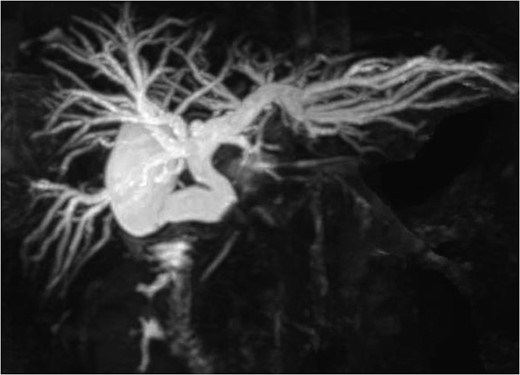

Before surgery, the stent tube was changed to an endoscopic nasobiliary drainage (ENBD) tube for intraoperative cholangiography. The initial intraoperative examination revealed the marked thickening of the gallbladder wall. First, the anterior wall of Hartmann’s pouch was excised to remove the impacted gallstone (Fig. 3). After the removal of the gallstone, a cholecystocholedochal fistula was identified. The gallbladder was then excised and the remaining neck portion was used to perform choledochoplasty using a gallbladder patch. The gallbladder patch was sutured to cover the anterior wall of the common hepatic bile duct (Fig. 4). Intraoperative cholangiography was performed to confirm the absence of bile leakage and bile duct stenosis.

The intraoperative findings: The anterior wall of the cystic duct and the common hepatic duct was dissected to remove the gallstone.